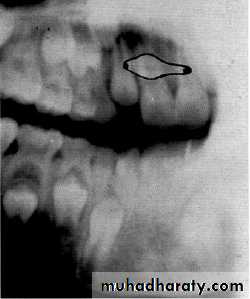

Is the maxillary second premolar (arrows) displaced to the buccal or the lingual?

premolar filmmolar film

premolar bitewing

4The tube head moves distally from the premolar film to the molar film. The second premolar also moves distally, overlapping the first molar more in the molar film. In moving from the premolar periapical to the bitewing, the tube head moves down and the premolar also moves down. The displacement is to the lingual.